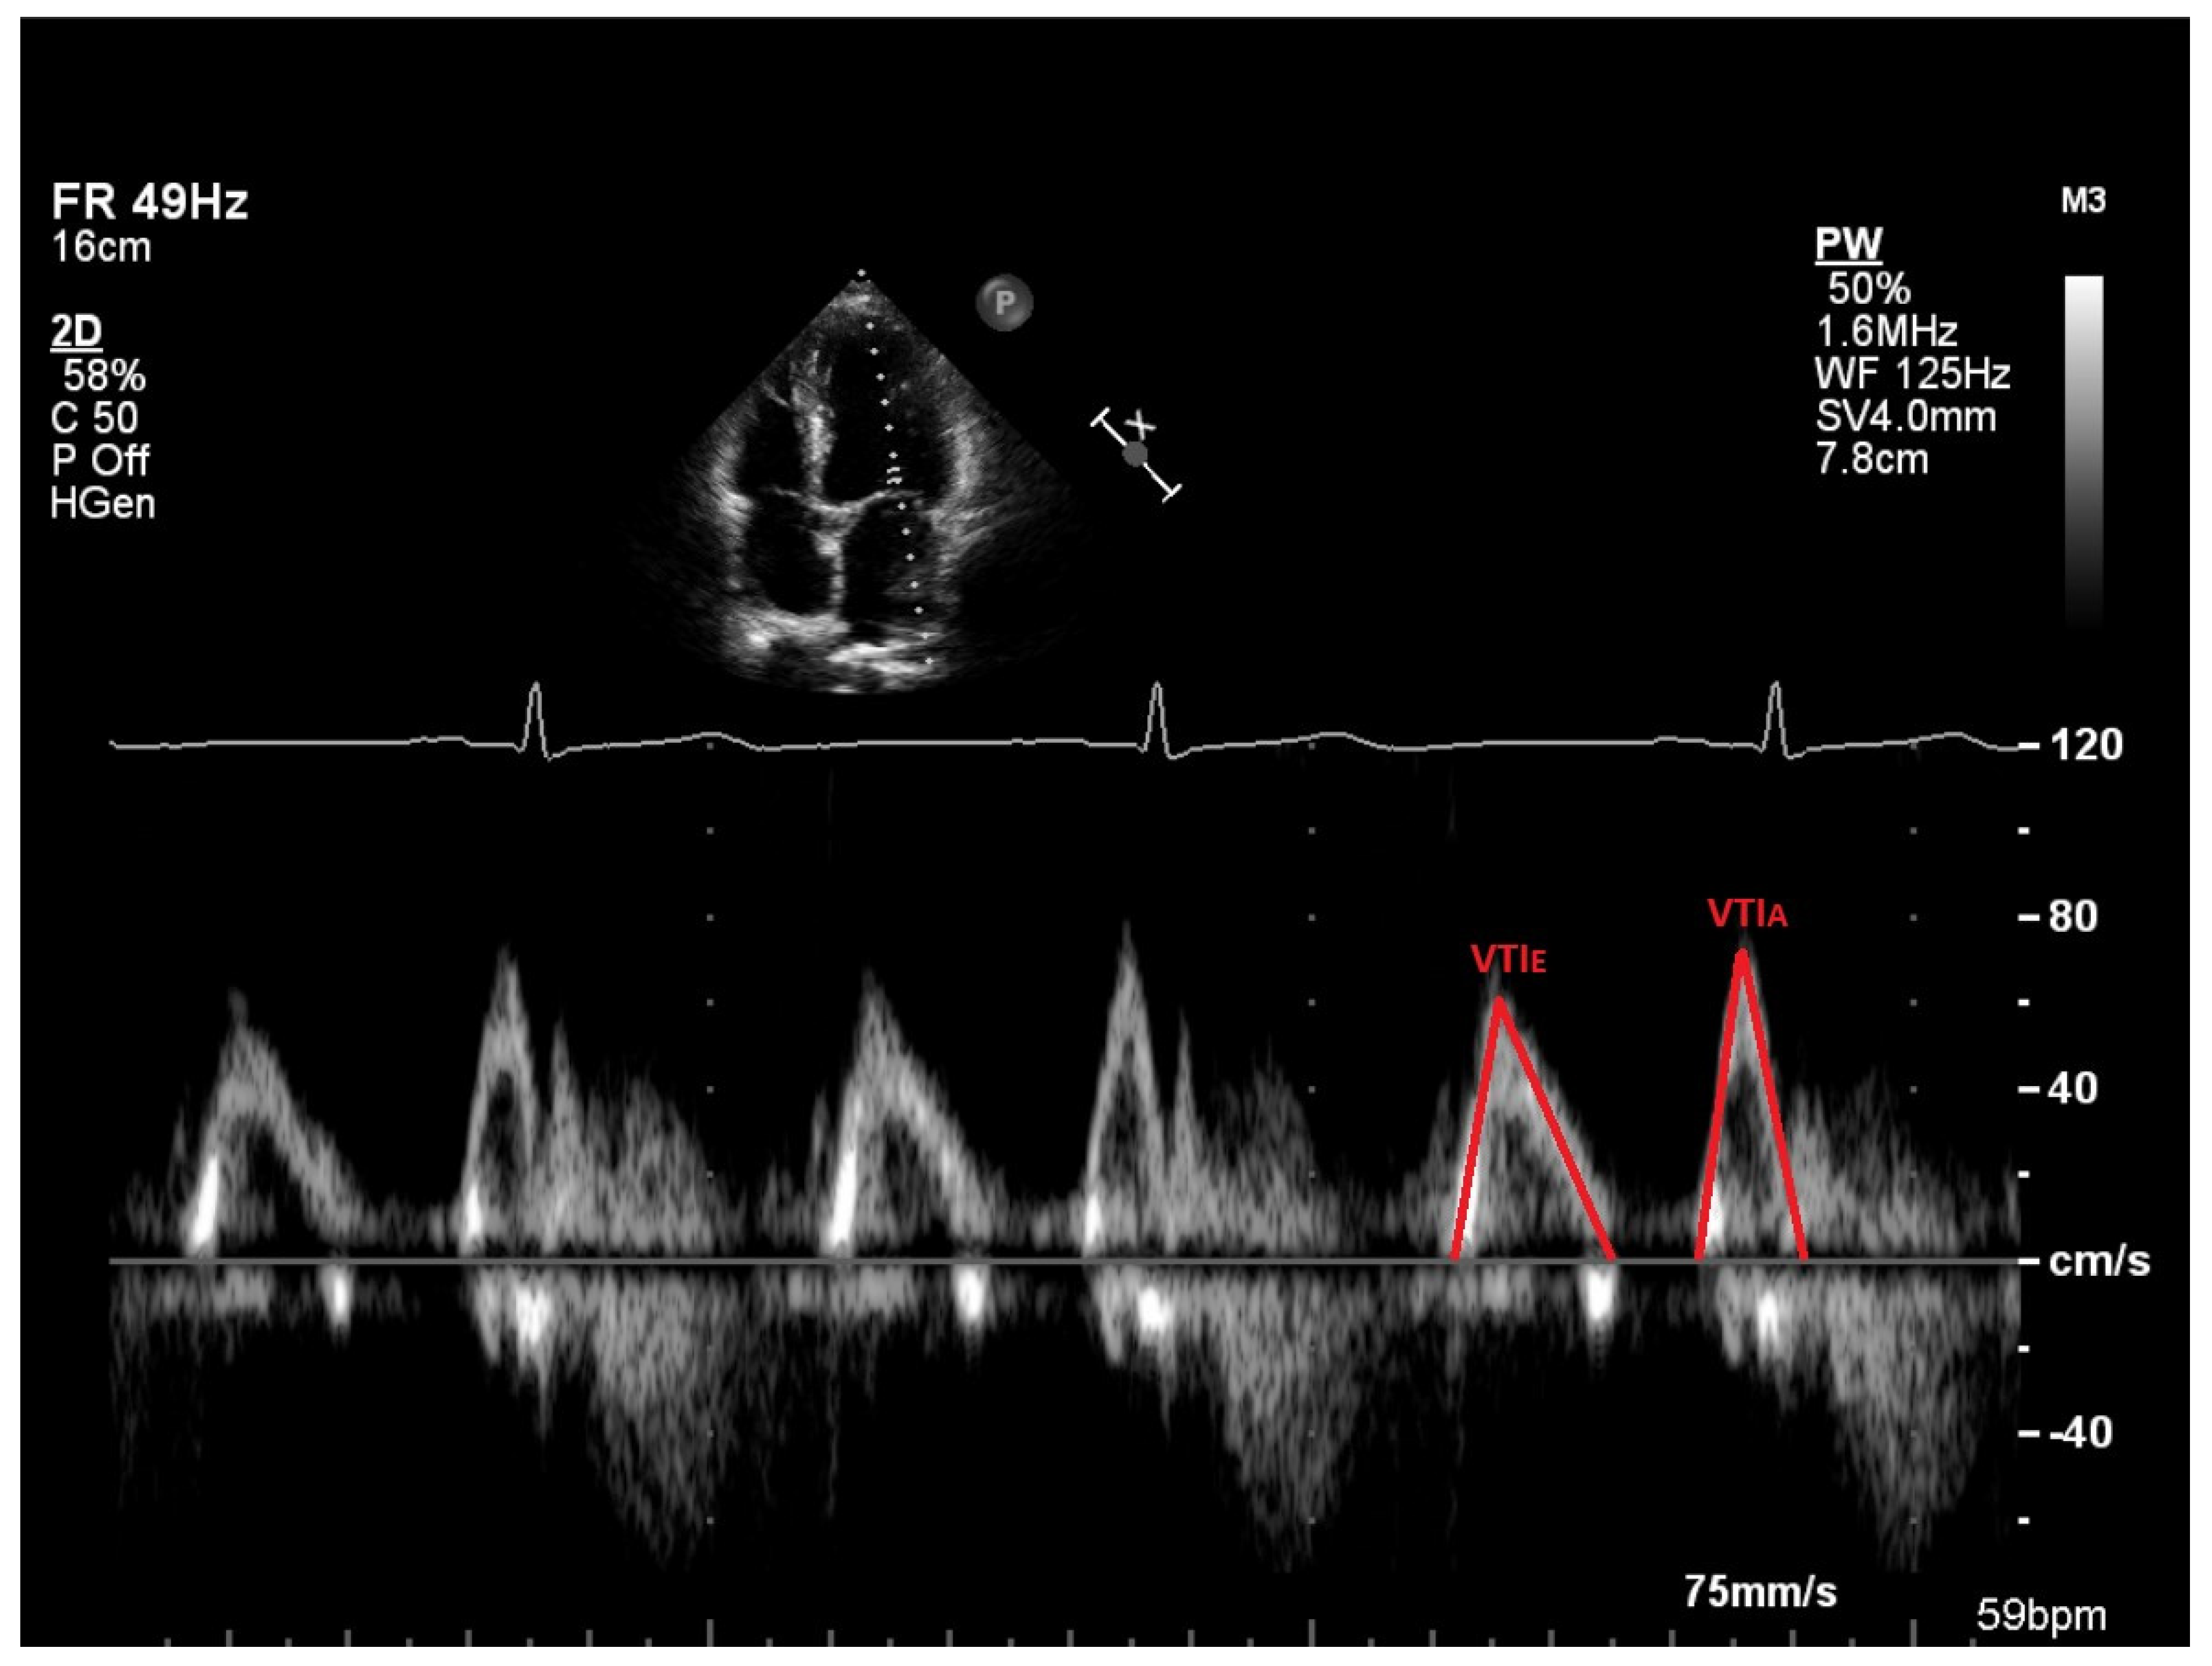

2.3. Vortex Formation and Vortex Formation Time

2.4. Transthoracic Echocardiography (TTE)

| VTI E (cm) | 11.8 (10.8–13.5) | 12.1 (11.2–13.3) | 0.761 | 2.5 |

| VTI A (cm) | 4.2 (3.4–5.0) | 4.9 (4.2–6.1) | 0.002 | 16.7 |

| VTI E (cm) | 10.5 (9.0–11.7) | 12.3 (10.6–14.8) | <0.001 | 17.1 |

| VTI A (cm) | 7.1 (6.2–7.5) | 7.5 (6.8–8.3) | <0.001 | 5.6 |